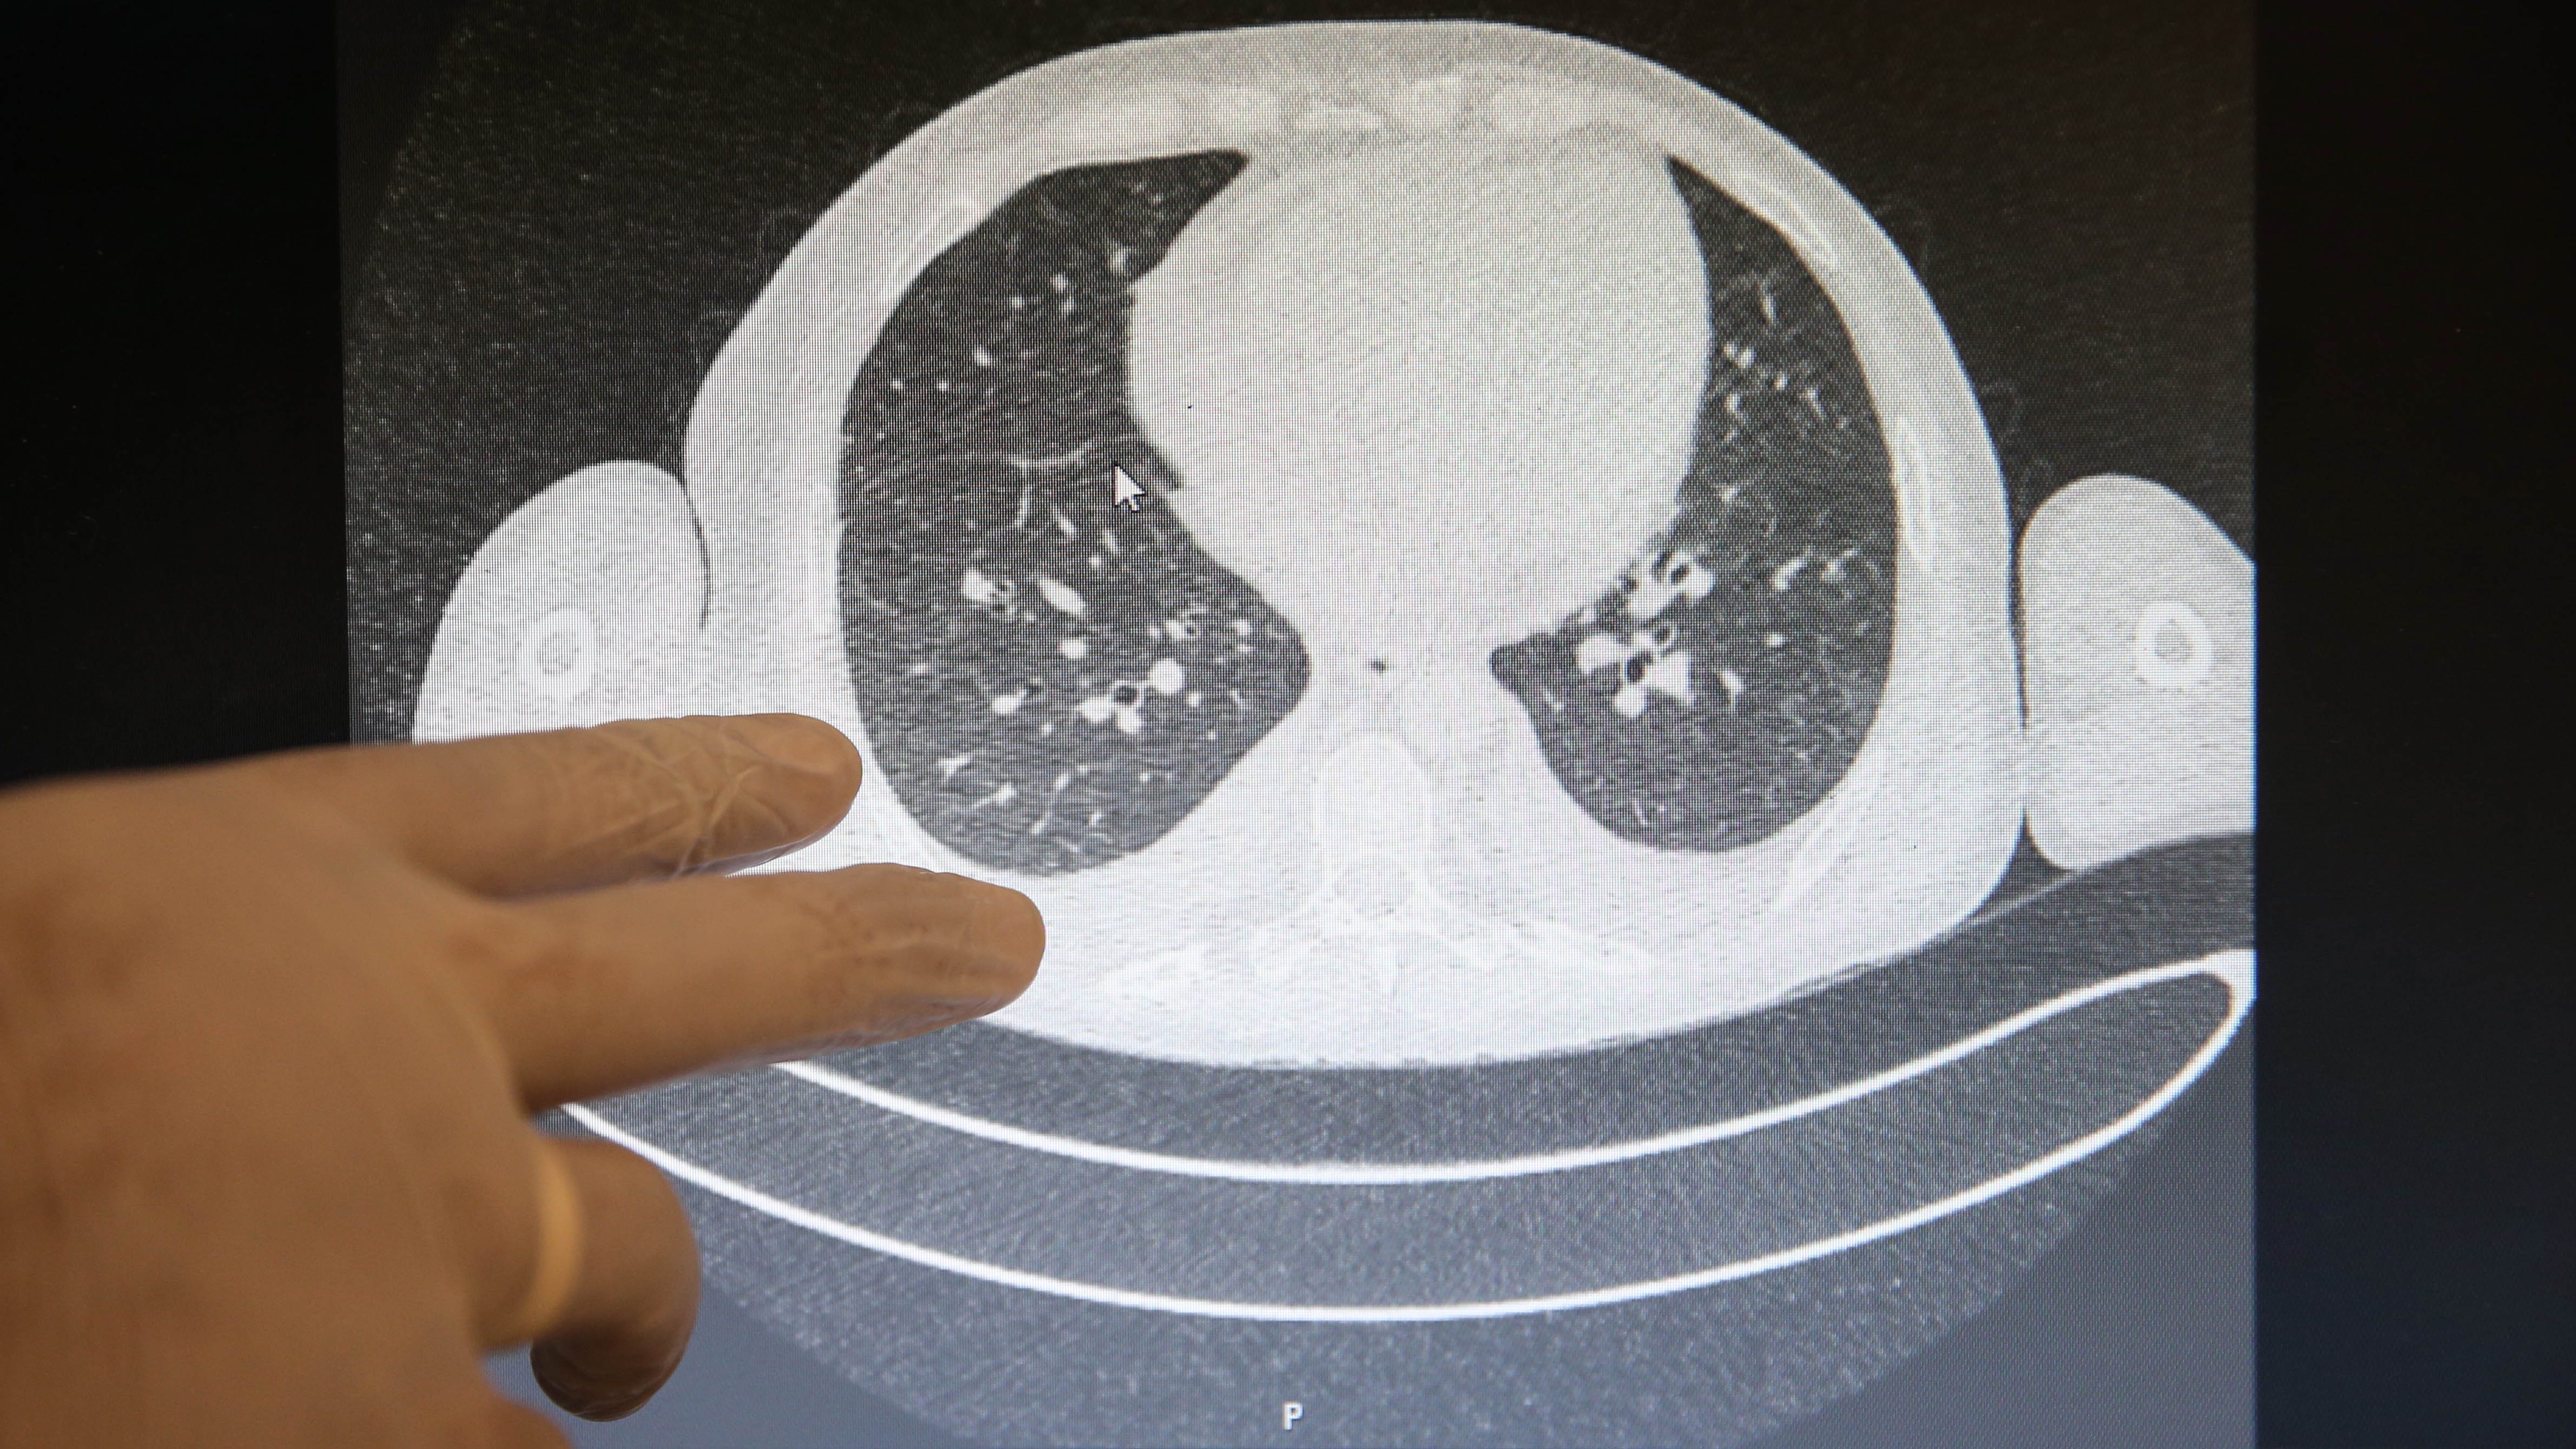

Özellikle nefes darlığı şikayetiyle başvurduğu hastanede akciğer tutulumu olduğu tespit edilen hastaların, tomografi görüntülerinde Kovid-19'un verdiği tahribat ortaya çıkıyor.

Görüntülerdeki beyazlıklarla Kovid-19'lu bir hastanın akciğerindeki tutulumlar, iltihap birikmeleri ve organın yapısının bozukluğu ortaya konuluyor. Normal hastaların ise akciğerindeki elastik yapı dikkati çekiyor.

Elastik yapıya sahip akciğerlerde Kovid-19 nedeniyle oluşan tahribatlar sonucu zaman zaman organın kapasitesi küçüldüğü için hasta iyileştikten sonra da nefes almakta güçlük çekip, yürümekte zorlanabiliyor.

Akdeniz Üniversitesi Hastanesi Acil Tıp Ana Bilim Dalı Başkanı Prof. Dr. Yıldıray Çete, AA muhabirine yaptığı açıklamada, nefes darlığıyla gelen hastanın akciğerinde tutulum görebildiklerini belirterek, "Bu hastaların oksijen düzeyleri düşüyor. Oksijen düşmesinin getirdiği ciddi bir kaygı bozukluğu ve nefes açlığı oluyor. En ufak hareket efor kapasitelerini sınırlıyor. Hastalar, daha çok yatağın içinde oturarak derin nefes almaya çalışıyor, konuşurken bile yoruluyor." dedi.

"Elastik bir yapısı olan akciğer dokusunda sertleşme ve yapısında bozulma olabiliyor. Bu hastalık geçen yıl kasımda ortaya çıktı. Hastalarımızı daha bir yıl bile takip edemedik. Türkiye verilerini daha mart ayında aldık. Uzun dönemli etkilerini dünya bilmiyor ama bazı yayınlar şunu gösteriyor; Kovid-19 hastalığını kapan ve akciğer tutulumu olan bazı bireylerde ileri dönemlerde fibrozis (akciğer sertleşmesi) dediğimiz bir tablo oluşuyor. Akciğer dokusu elastik bir yapı, genişlemeye ve büzüşmeye müsait bir organ. Koronavirüs nedeniyle akciğerde fibrozis gelişince büzüşme ve genişleme olmuyor. Bu yüzden akciğer kapasitesi ve kişinin efor kapasitesi azalıyor. Eski fonksiyonel kapasitelerine dönemiyorlar. Bu ne kadar hastada oluyor, niye bazılarında oluyor bunu henüz bilmiyoruz."